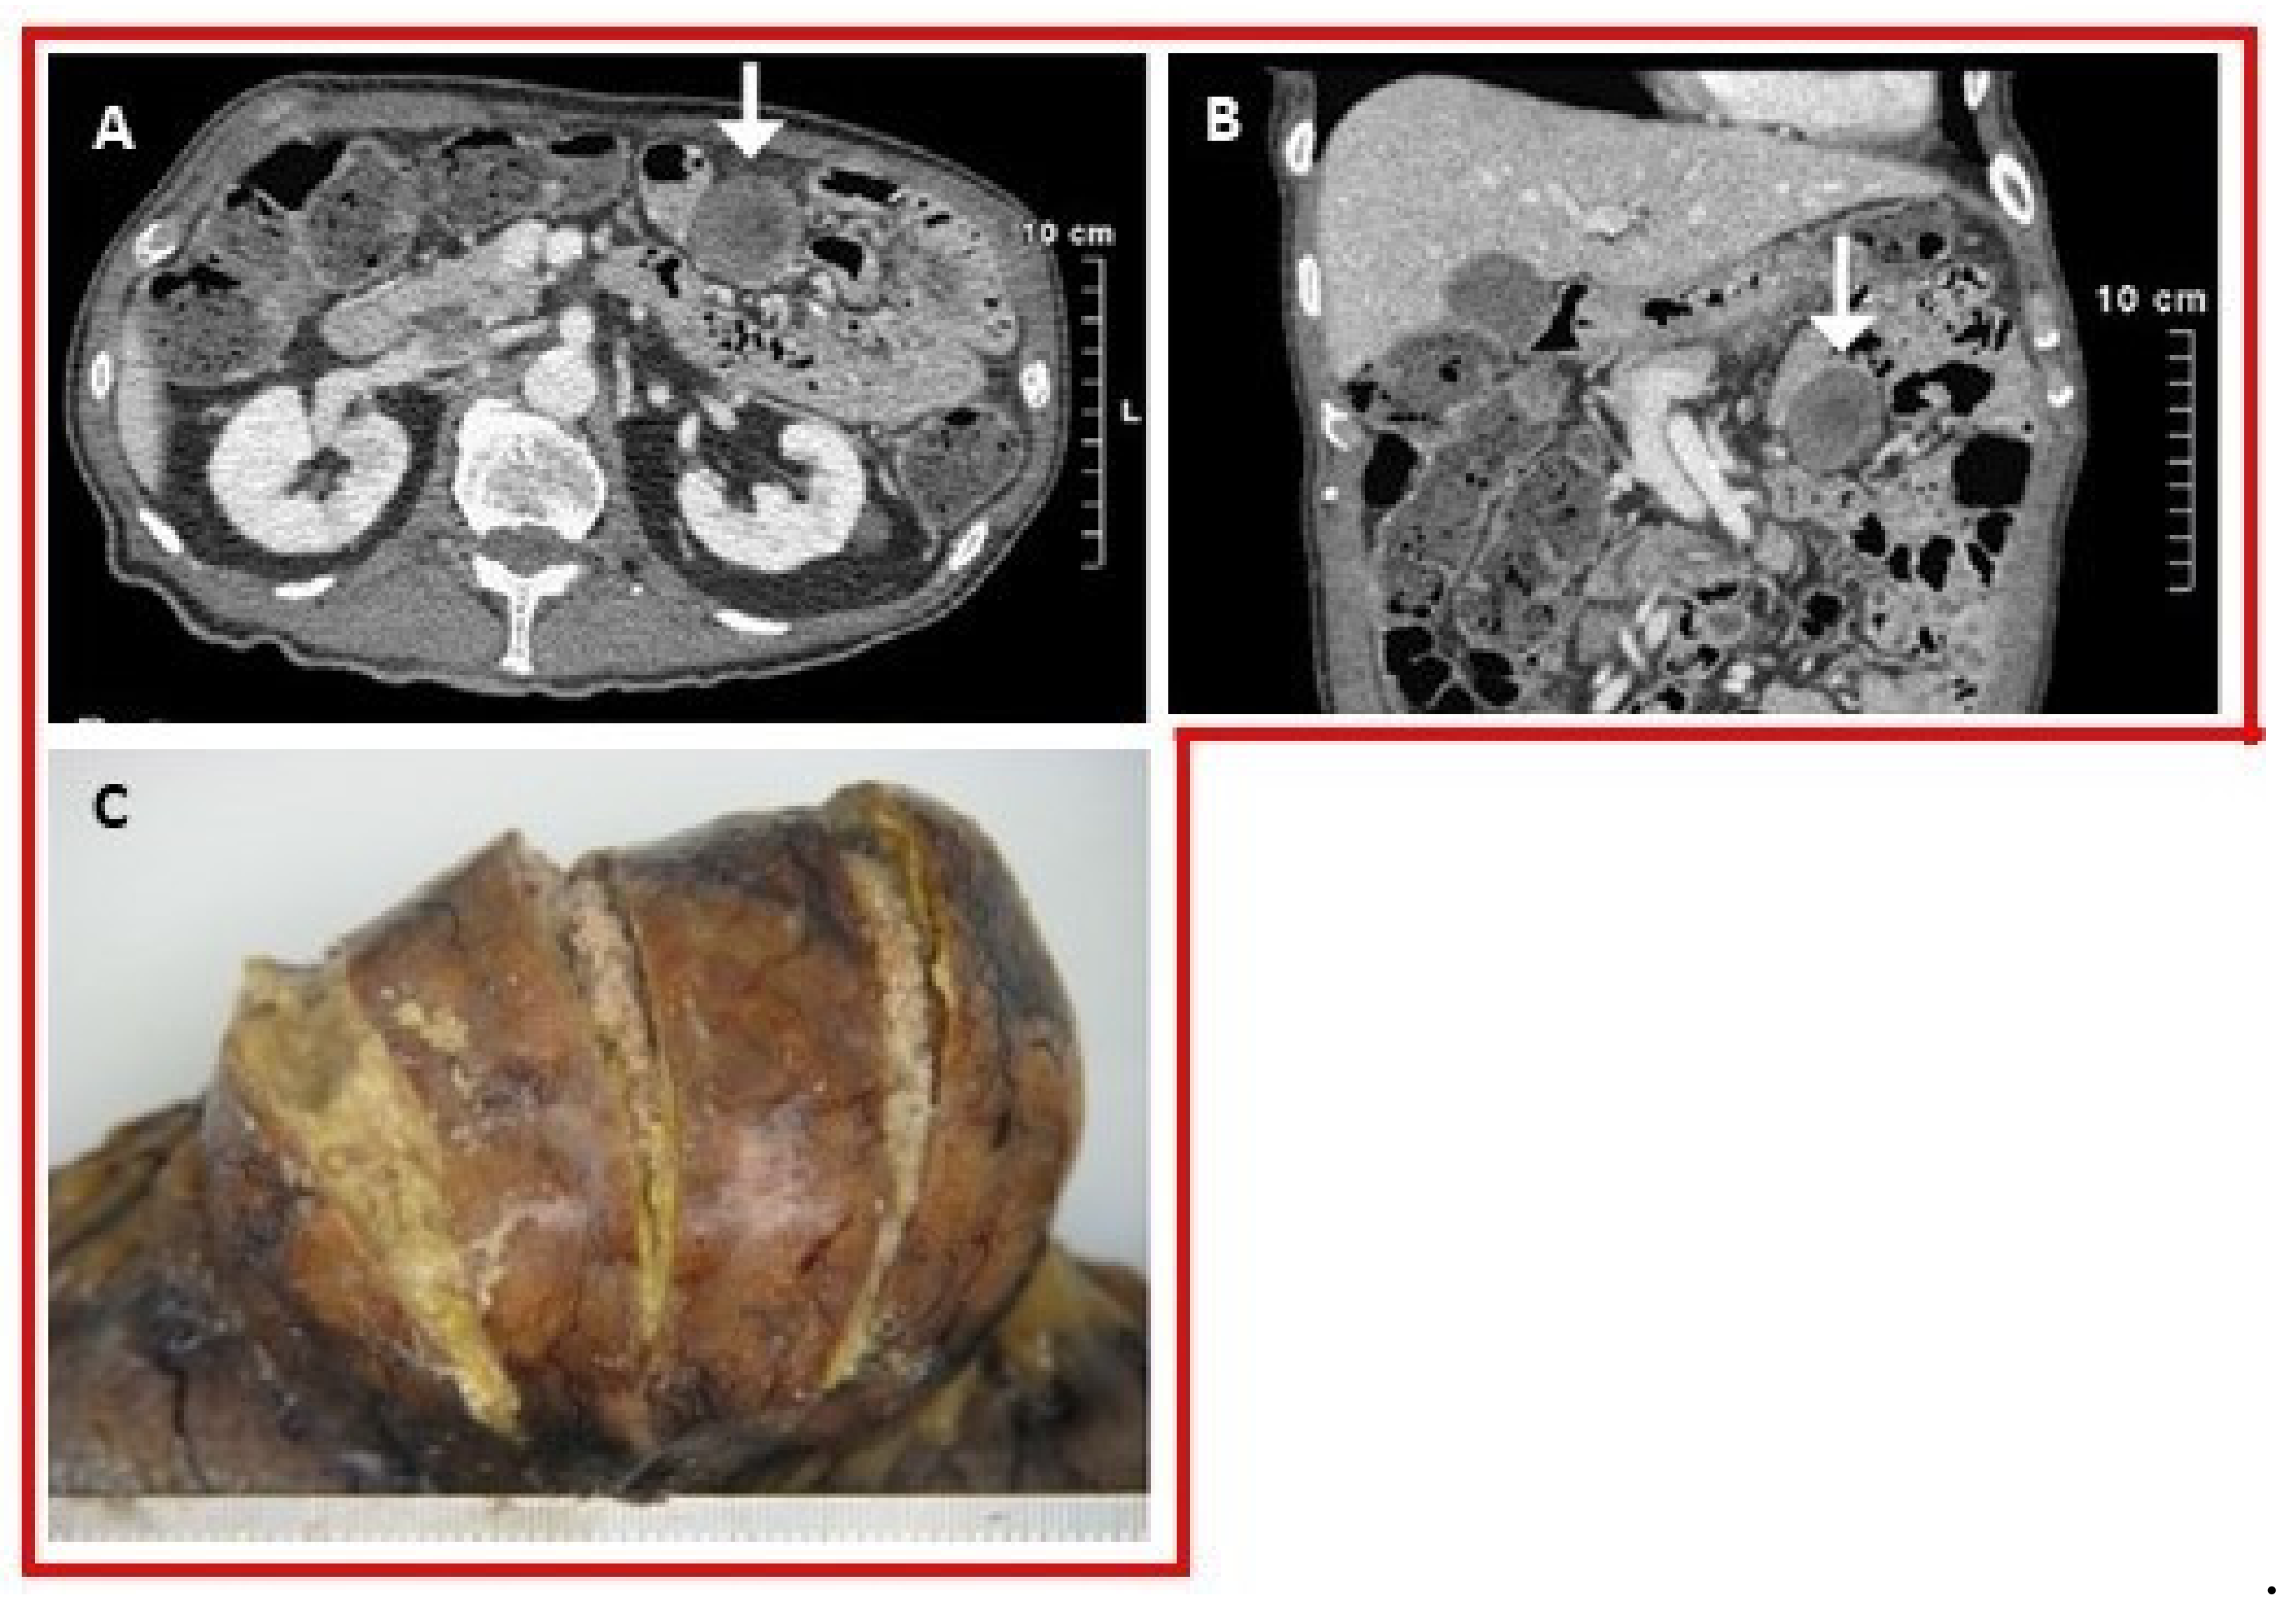

- Ministrini, S.; Baronio, G.; Zorzi, F.; Bercich, L.; Grazioli, L.; Molfino, S.; Portolani, N. Unusual presentation of gouty tophus in the liver with subsequent appearance in the same site of HCC: A correlate diagnosis? Case Report. World J. Surg. Oncol. 2019, 17. [Google Scholar] [CrossRef]

- Khanna, D.; Tang, S.-J.; Wallace, W.D.; Roth, B.E.; Hahn, B.H. Gouty tophi in a pancreatic pseudocyst. Arthritis Rheum. 2002, 46, 565–566. [Google Scholar] [CrossRef]

- Sarungbam, J.; Jain, S.; Yusuf, Y. Urate crystals in pancreatic pseudocyst: A rare cause of intestinal perforation. Am. J. Clin. Pathol. 2012, 138, A235. [Google Scholar] [CrossRef][Green Version]

- Chen, C.-H.; Chen, C.K.-H.; Yeh, L.-R.; Pan, H.-B.; Yang, C.-F. Intra-abdominal gout mimicking pelvic abscess. Skeletal Radiol. 2005, 34, 229–233. [Google Scholar] [CrossRef]